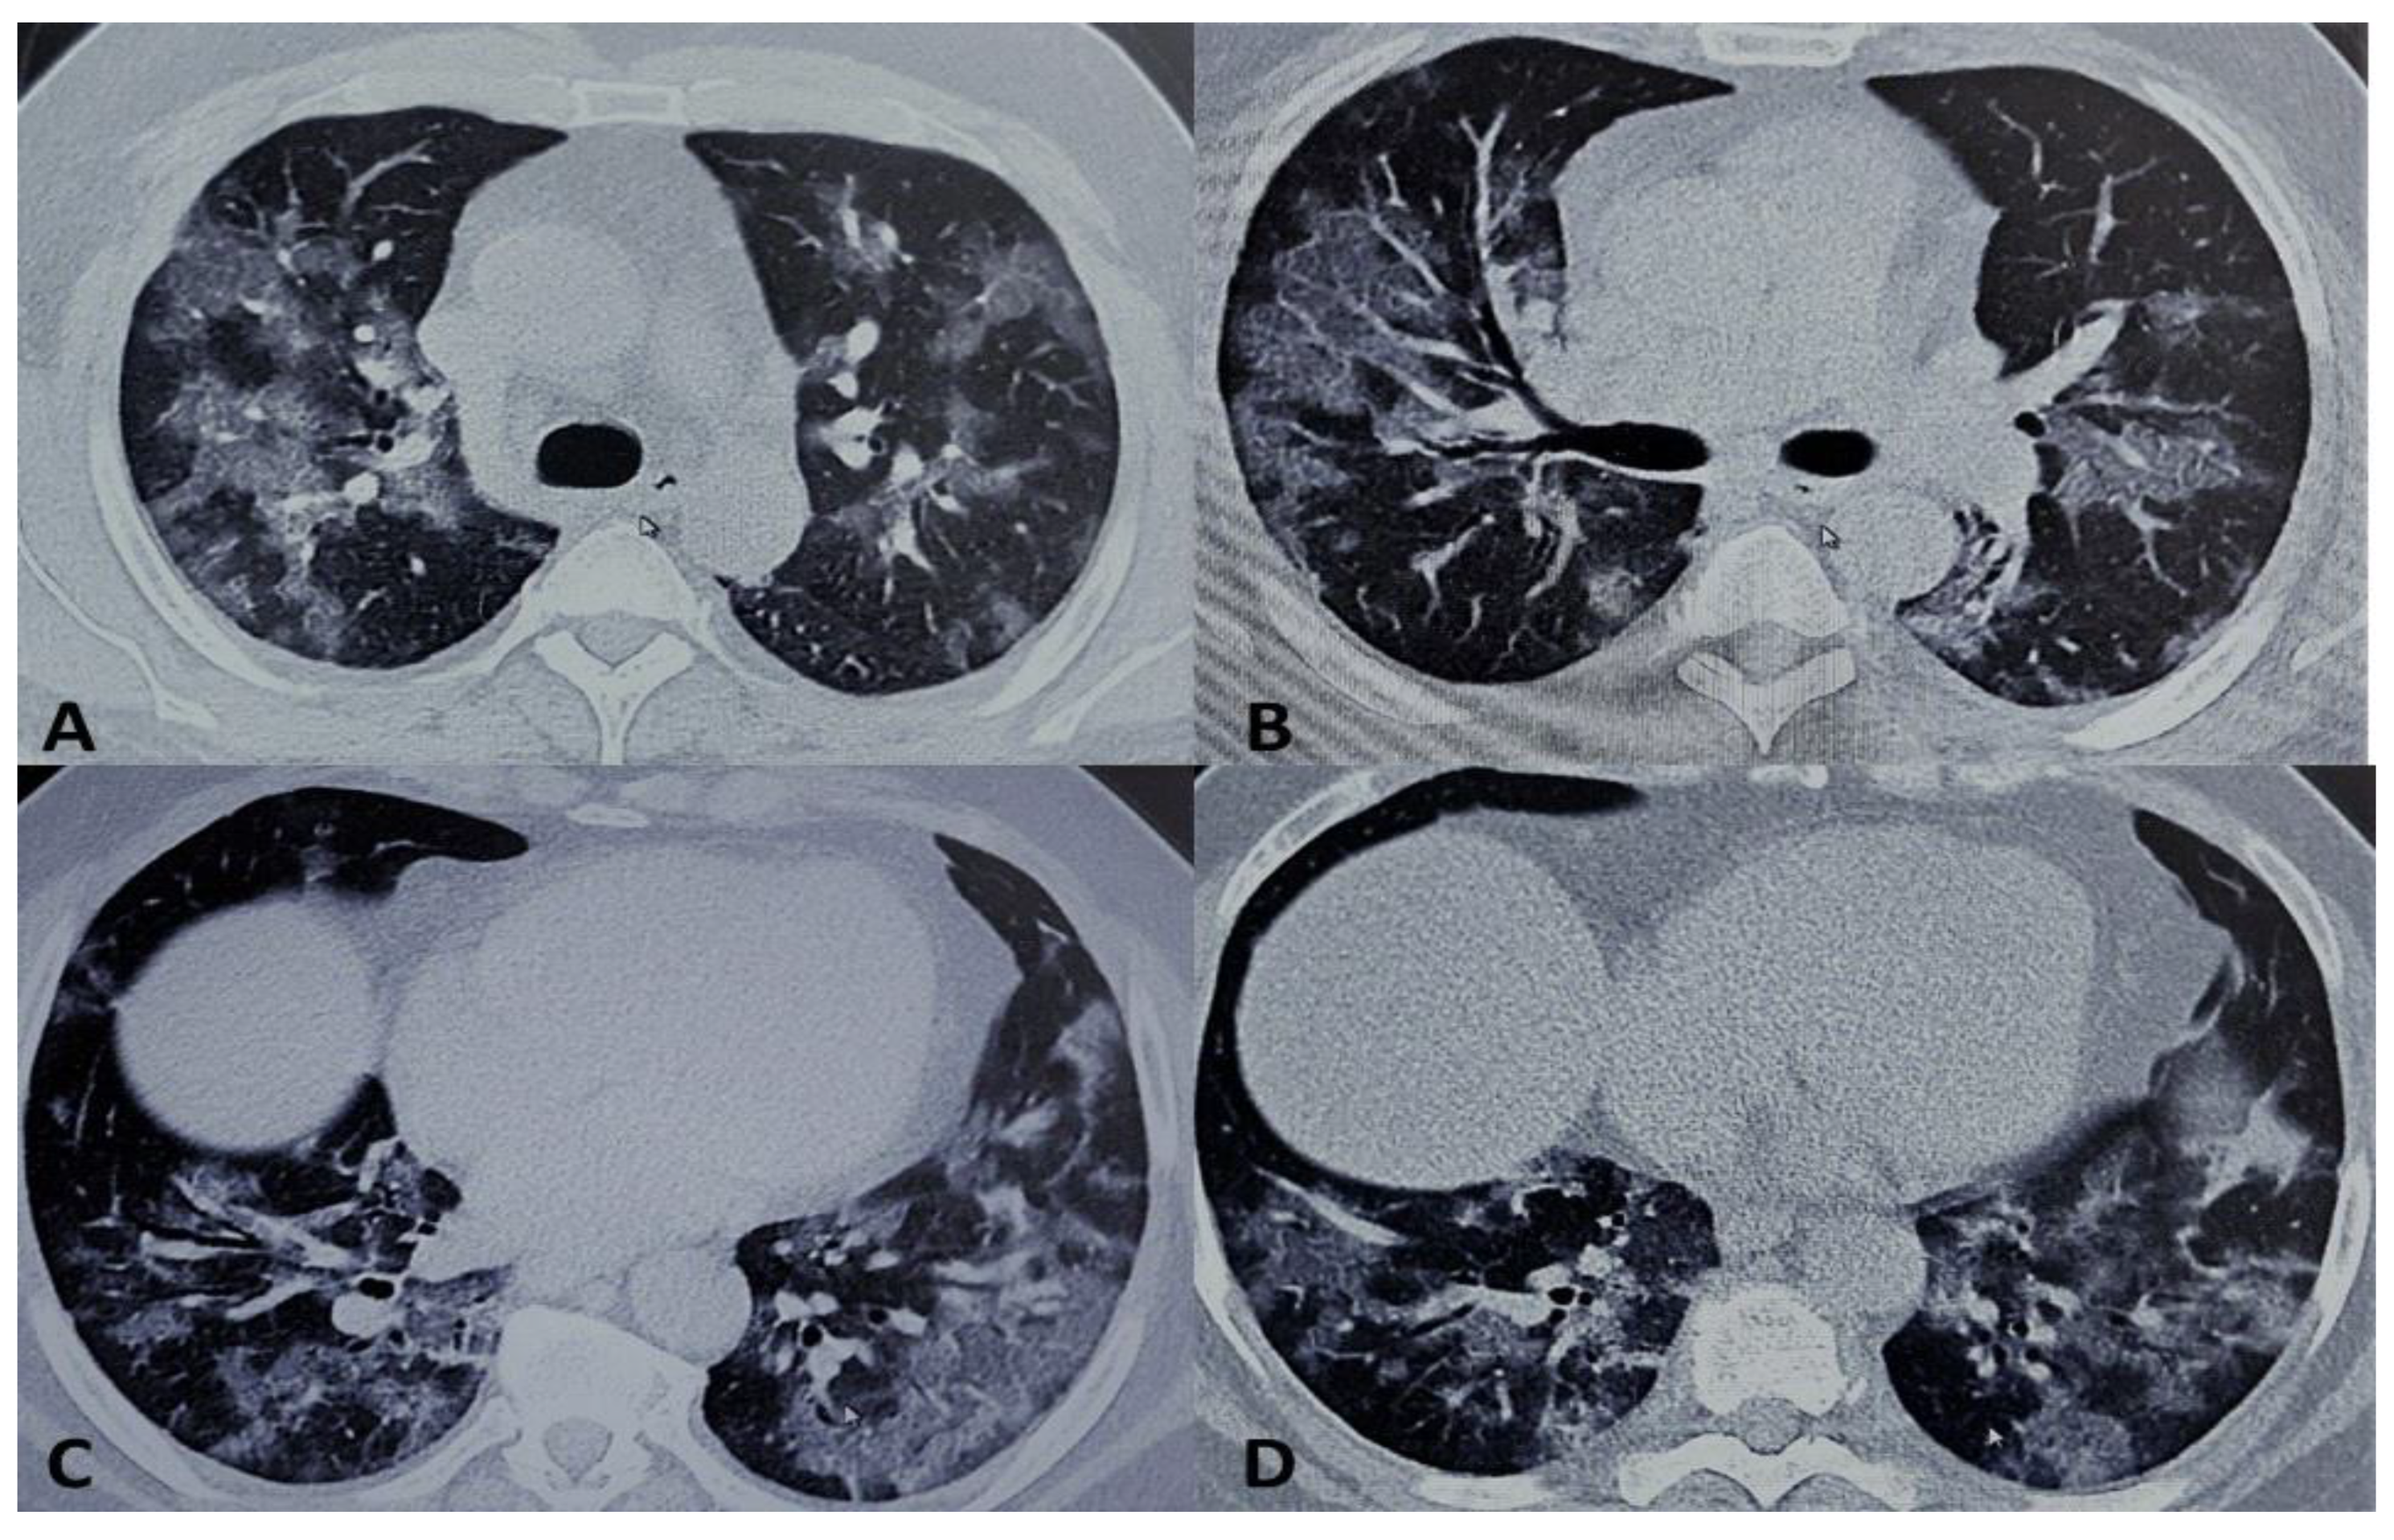

- Cellina, M.; Orsi, M.; Bombaci, F.; Sala, M.; Marino, P.; Oliva, G. Favorable Changes of CT Findings in a Patient with COVID-19 Pneumonia after Treatment with Tocilizumab. Diagn. Interv. Imaging 2020, 101, 323–324. [Google Scholar] [CrossRef] [PubMed]